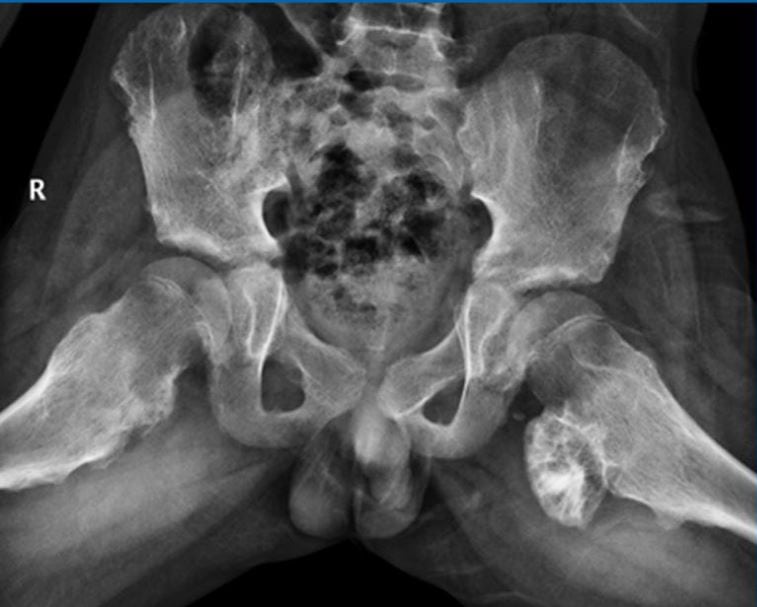

У половины пациентов остеохондрома обнаруживается в дистальном или проксимальном концах бедренной кости. У остальных 50% больных новообразованиями оказывались поражены и другие отделы скелета.

- множественные (остеохондроматозис). Такая мультицентрическая форма патологии обычно обусловлена генетической предрасположенностью. Множественные уплотнения выглядят, как бугорки, покрытые блестящей фибриновой оболочкой, существенно разнятся формой и локализацией.

На рентгенографических изображениях хорошо просматриваются измененные контуры бедренной кости. Визуализируются и очертания новообразования — четкие, непрерывные. С помощью рентгенологического исследования не удается рассмотреть сформировавшуюся хрящевую оболочку, только если в ней нет очагов кальцификации. При подозрении на укрупнение хрящевого слоя пациентам назначается МРТ.

Дифференциальная диагностика проводится для исключения остеомы, паростальной остеосаркомы, паростальной костно-хрящевой пролиферации и хондросаркомы, возникающей вследствие озлокачествления остеохондромы.